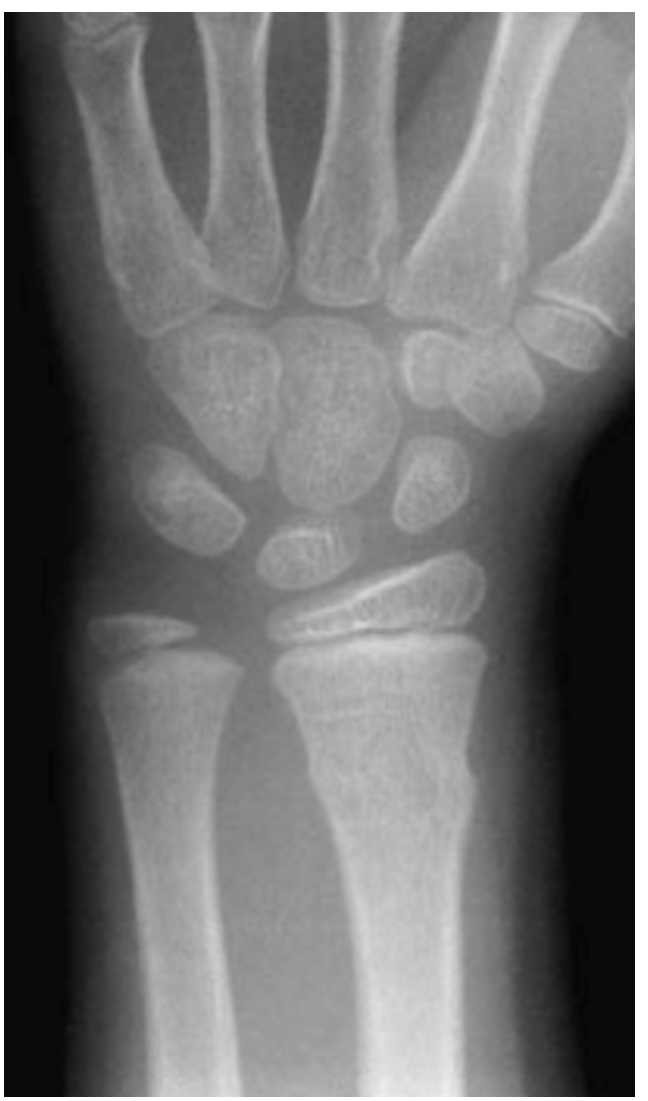

L Esame Radiografico Del Polso Radiologia Ortopedica

Image Radiografia Del Polso Sinistro Manuali Msd Edizione Professionisti